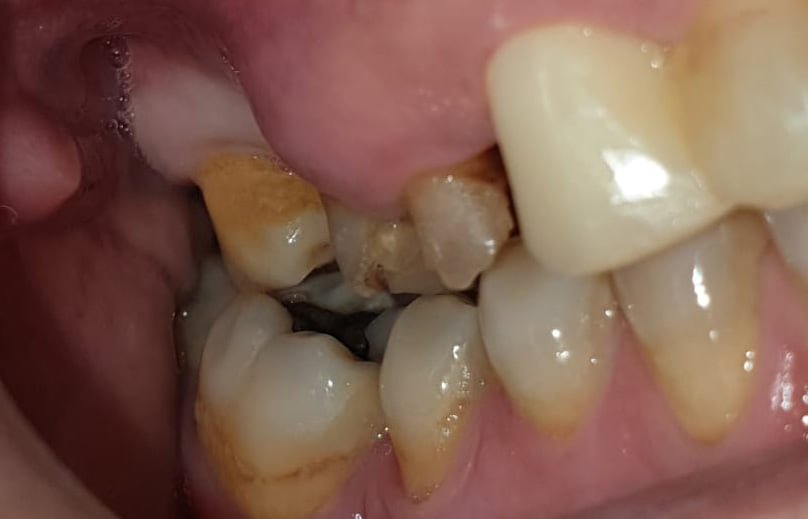

From the first radiographic examination (OPT and CT scan) there is an evident periapical granuloma and pain with pressure on 14 and 15, while 17 element is parodontopathic, moreover there is a lack of bone in 16 and 17 area with chronic infections at the level of the maxillary sinus. Due to the clinical history of the patient it was not advisable to go for a sinus lift, it has been planned the insertion of a pterygo implant and 2 post extractive EV implants. During the surgery, biomaterial (Novocor from B&B Dental) was added to the insertion of the implants to remodel the ridge horizontally, given the evident bone deiescence. Two temporary provisional titanium abutments were then inserted, welded with a two titanium bar. We inserted 2 EV implants to reach a better primary stability. As the patient is bruxist the crowns have been totally unloaded. The pterygoid implant will be loaded on a second session.